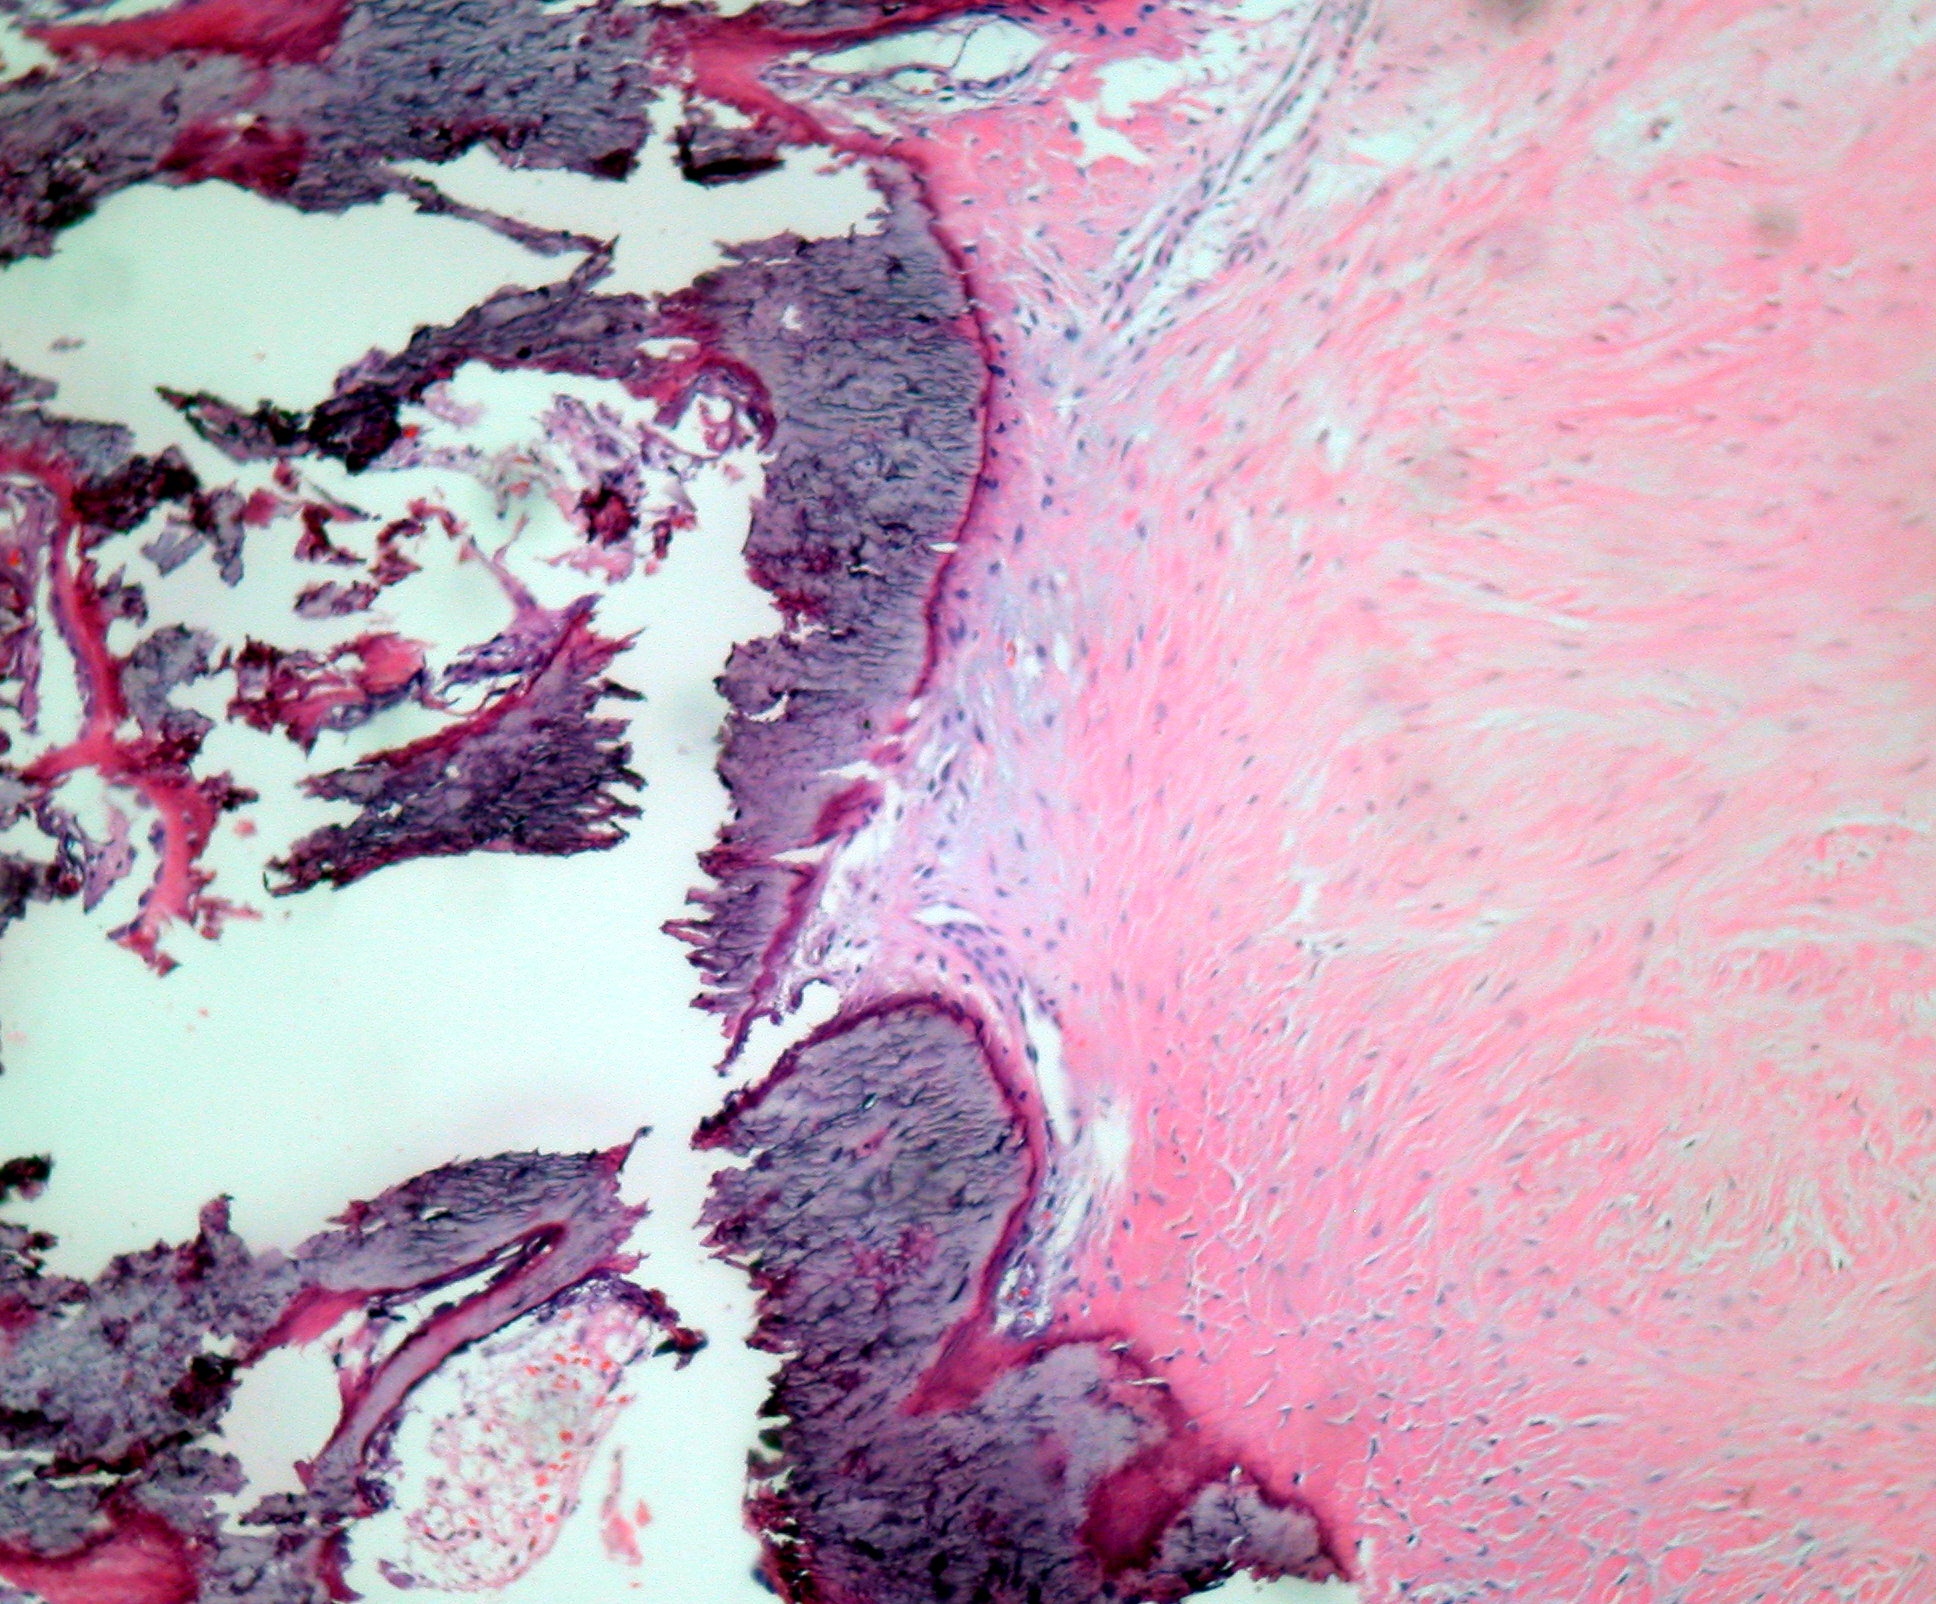

Abstract: Desmoid tumor (DT) or aggressive fibromatosis is a rare type of soft tissue neoplastic disorder that does not metastasize, but is highly infiltrative of adjacent muscle and aponeurosis. Treatment must be aggressive, and consists mainly of surgical resection with free margins, although radiotherapy, non-steroidal anti-inflammatory drugs, hormones and chemotherapy may be used. Local relapse rate after primary treatment is high. We report a patient who had a relapse of DT on the dorsum, and who underwent thoracotomy, apophysectomy, osteotomy, biopsy of the left lower lobe of the lung, closed pleural space drainage, immediate reconstruction with rotation of muscle flaps and mesh repair. After surgery, the patient received 23 cycles of radiotherapy associated with tamoxifen (40 mg/day).

Key words: desmoid tumor – chest wall – wide surgical resection